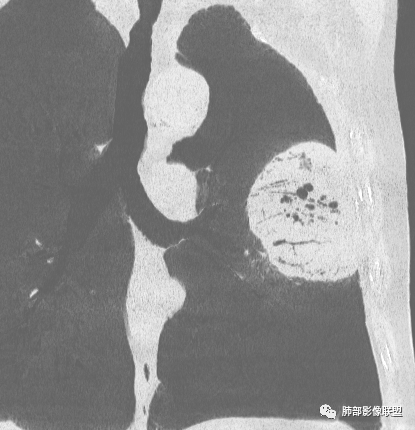

增强没有强化,血管束正常,气管束有正常有扩张,内有空洞,考虑炎性病变,隐球?

左肺团块样病灶,分叶,膨隆,不规则空洞,支气管枯枝样,血管造影征,考虑恶性,腺癌(肺肠型)。

糖尿病史,慢性病程,左肺巨大肿块,跨叶生长,肿块近端可见充气支气管征及悬浮气泡,轻度圴匀强化,病变长轴与胸膜平行,炎性标志物正常,考虑放线菌,其次淋巴瘤

我再建一下血管。支气管进入,但是近端推移,堵塞

内部支气管扩张

回头看,内部支气管近端其实不连续,伴随肺动脉不存在

4)密度:肿块平扫为软组织密度,由于体积较大,内部常见大片状坏死,可出现不规则厚壁空洞或坏死内多发无壁小空洞,坏死多不均匀:坏死灶内可见如柳絮样的斑片样强化灶,坏死边缘与非坏死区分界不清本例坏死较明显,密度不均匀。

5)肿瘤强化方式:肺部恶性肿瘤强化程度与其血供丰富程度相关,血供丰富多强化明显,反之则较差。由于PSC 周边实性部分富血供及内部黏液变性、坏死,增强后肿块多数呈轻-中度边缘环形强化或不均匀小斑片状强化。国外学者对照病理发现肿瘤细胞或胶原组织增强扫描时强化,无强化的低密度区代表了黏液样变性区和出血坏死区。